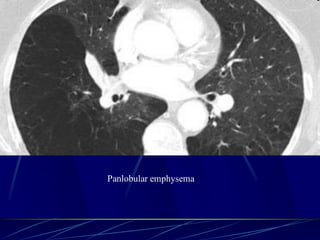

Panlobular emphysema

Affects the whole secondary lobule

Lower lobe predominance

In alpha-1-antitrypsin deficiency, but

also seen in smokers with advanced

emphysema

Affects the entire secondary pulmonary

lobule and is more pronounced in the lower

zones

Complete destruction of the entire pulmonary

lobule.

Results in an overall decrease in lung

attenuation and a reduction in size of

pulmonary vessels

83